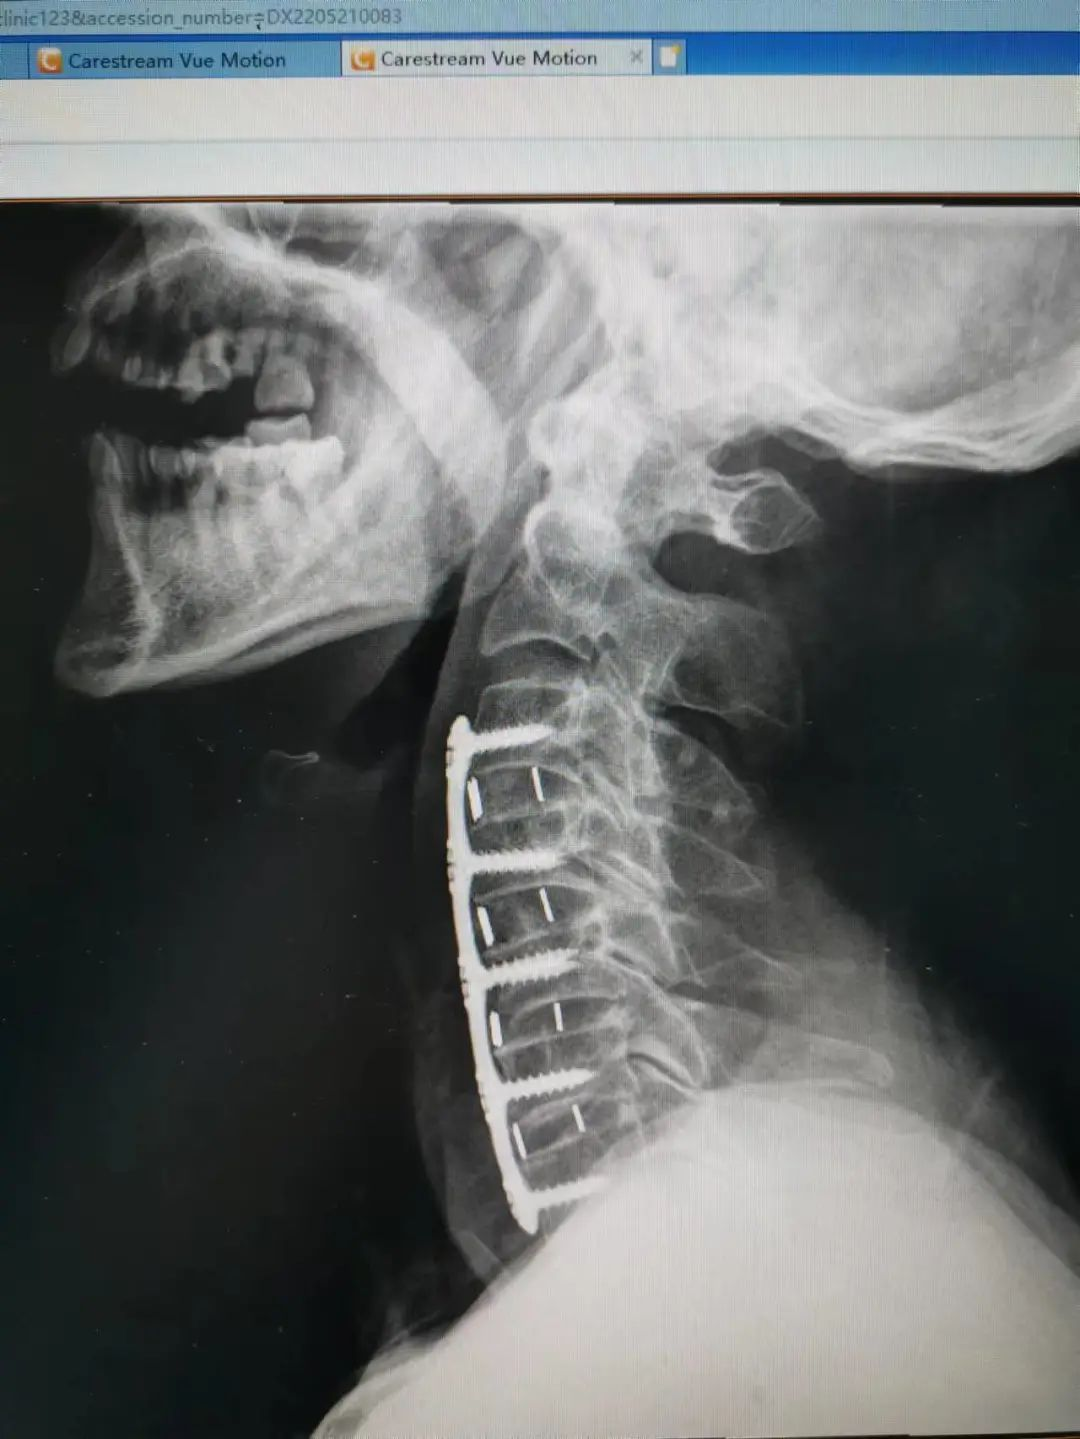

楊先生脊髓性頸椎病拍片

由于楊先生的病情嚴(yán)重,需住院治療。楊先生入院后,瀘州市中醫(yī)醫(yī)院骨傷二科科主任楊陳一制定了手術(shù)計(jì)劃,決定脊髓型頸椎病的手術(shù)從前路切開減壓,頸3/4 、頸4/5、 頸5/6、 頸6/7椎間盤切除,椎間融合,鋼板內(nèi)固定術(shù)手術(shù),而腰椎管狹窄癥經(jīng)后路切開減壓,腰3/4、腰4/5椎同盤動(dòng)除,椎間融合、釘棒系統(tǒng)內(nèi)固定術(shù)。

楊先生術(shù)后拍片